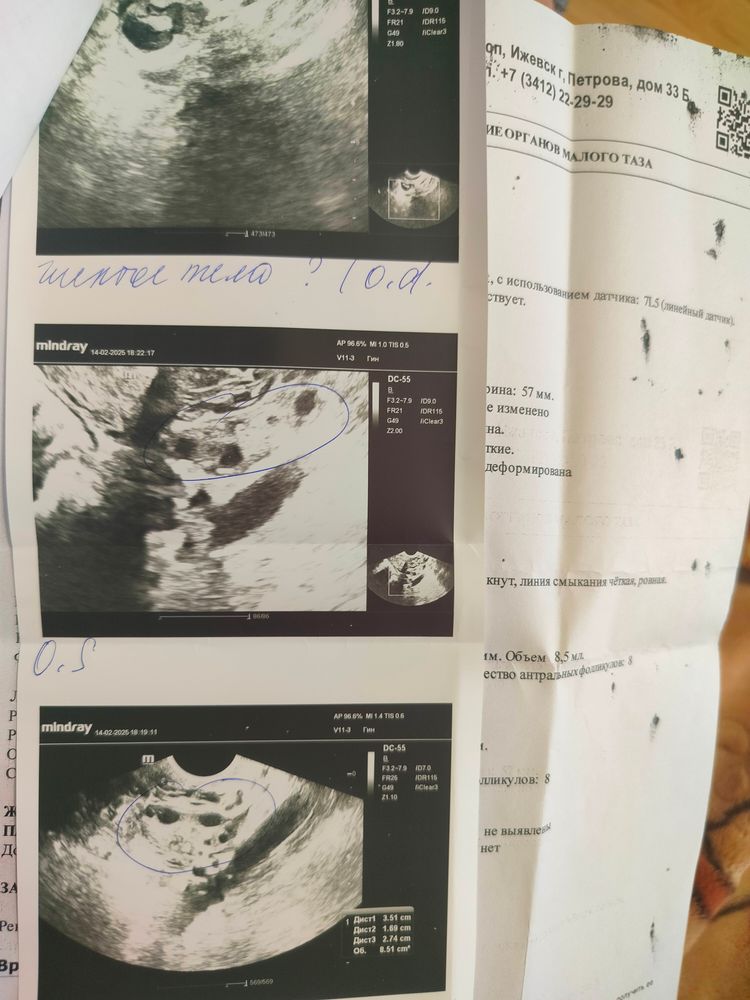

11.02.25. Эндометрий 13,1. В ЛЯ : антральные фолликулы 14, В ПЯ : колич астральных фолликулов во всём объёме Я 13. Строение не изменено за счёт округлого анэхогенного включения с чёткими и ровными контурами, при ЦДК (-) аваскулярный, размерами 18*17мм (персистенция фолликула?). Жидк не определяется. УЗ-признаки ановуляторного цикла. Эхогенность понижена, не соотв менстр циклу. Выписала дюфастон с 11-25 дц.

14.02 решила всё таки проверить, что моим фолликом. Пошла на УЗИ. Эндометрий 14мм, эхогенность изоэхогенна, при ЦДК кровоток не лоцируется, ЖТ под вопросом. Причём она так и сказала, то ли фоллик то ли ЖТ, в ПЯ фол 8х8,5, в ЛЯ 8х6мм.